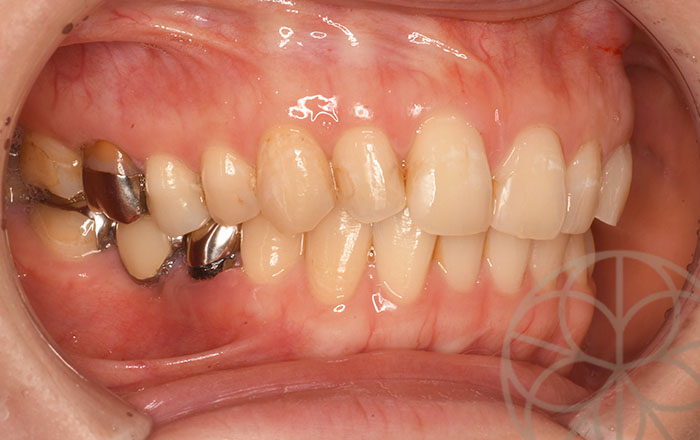

治療後

自信をもって笑えるようになりました。喜びの声をいただきました。